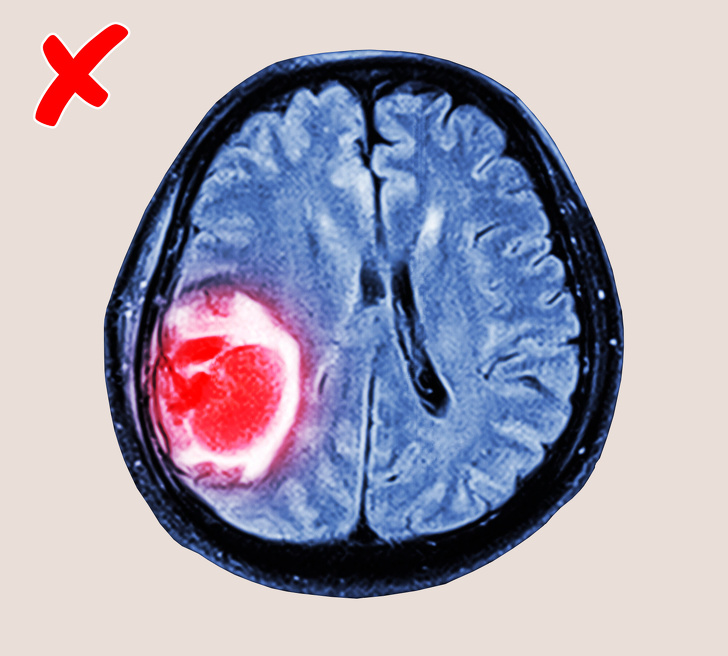

Бонус: мобільні телефони не викликають рак

Більшість людей упевнено, що мобільні телефони можуть викликати рак мозку. Однак у нас хороша новина: дослідження не підтвердили зв'язку між електромагнітними сигналами від мобільних телефонів і розвитком ракових пухлин. 10 років вчені займалися вивченням цього питання і прийшли до висновку, що радіочастотні випромінювання, впливу яких ми піддаємося, користуючись мобільним зв'язком, нешкідливі для нас.